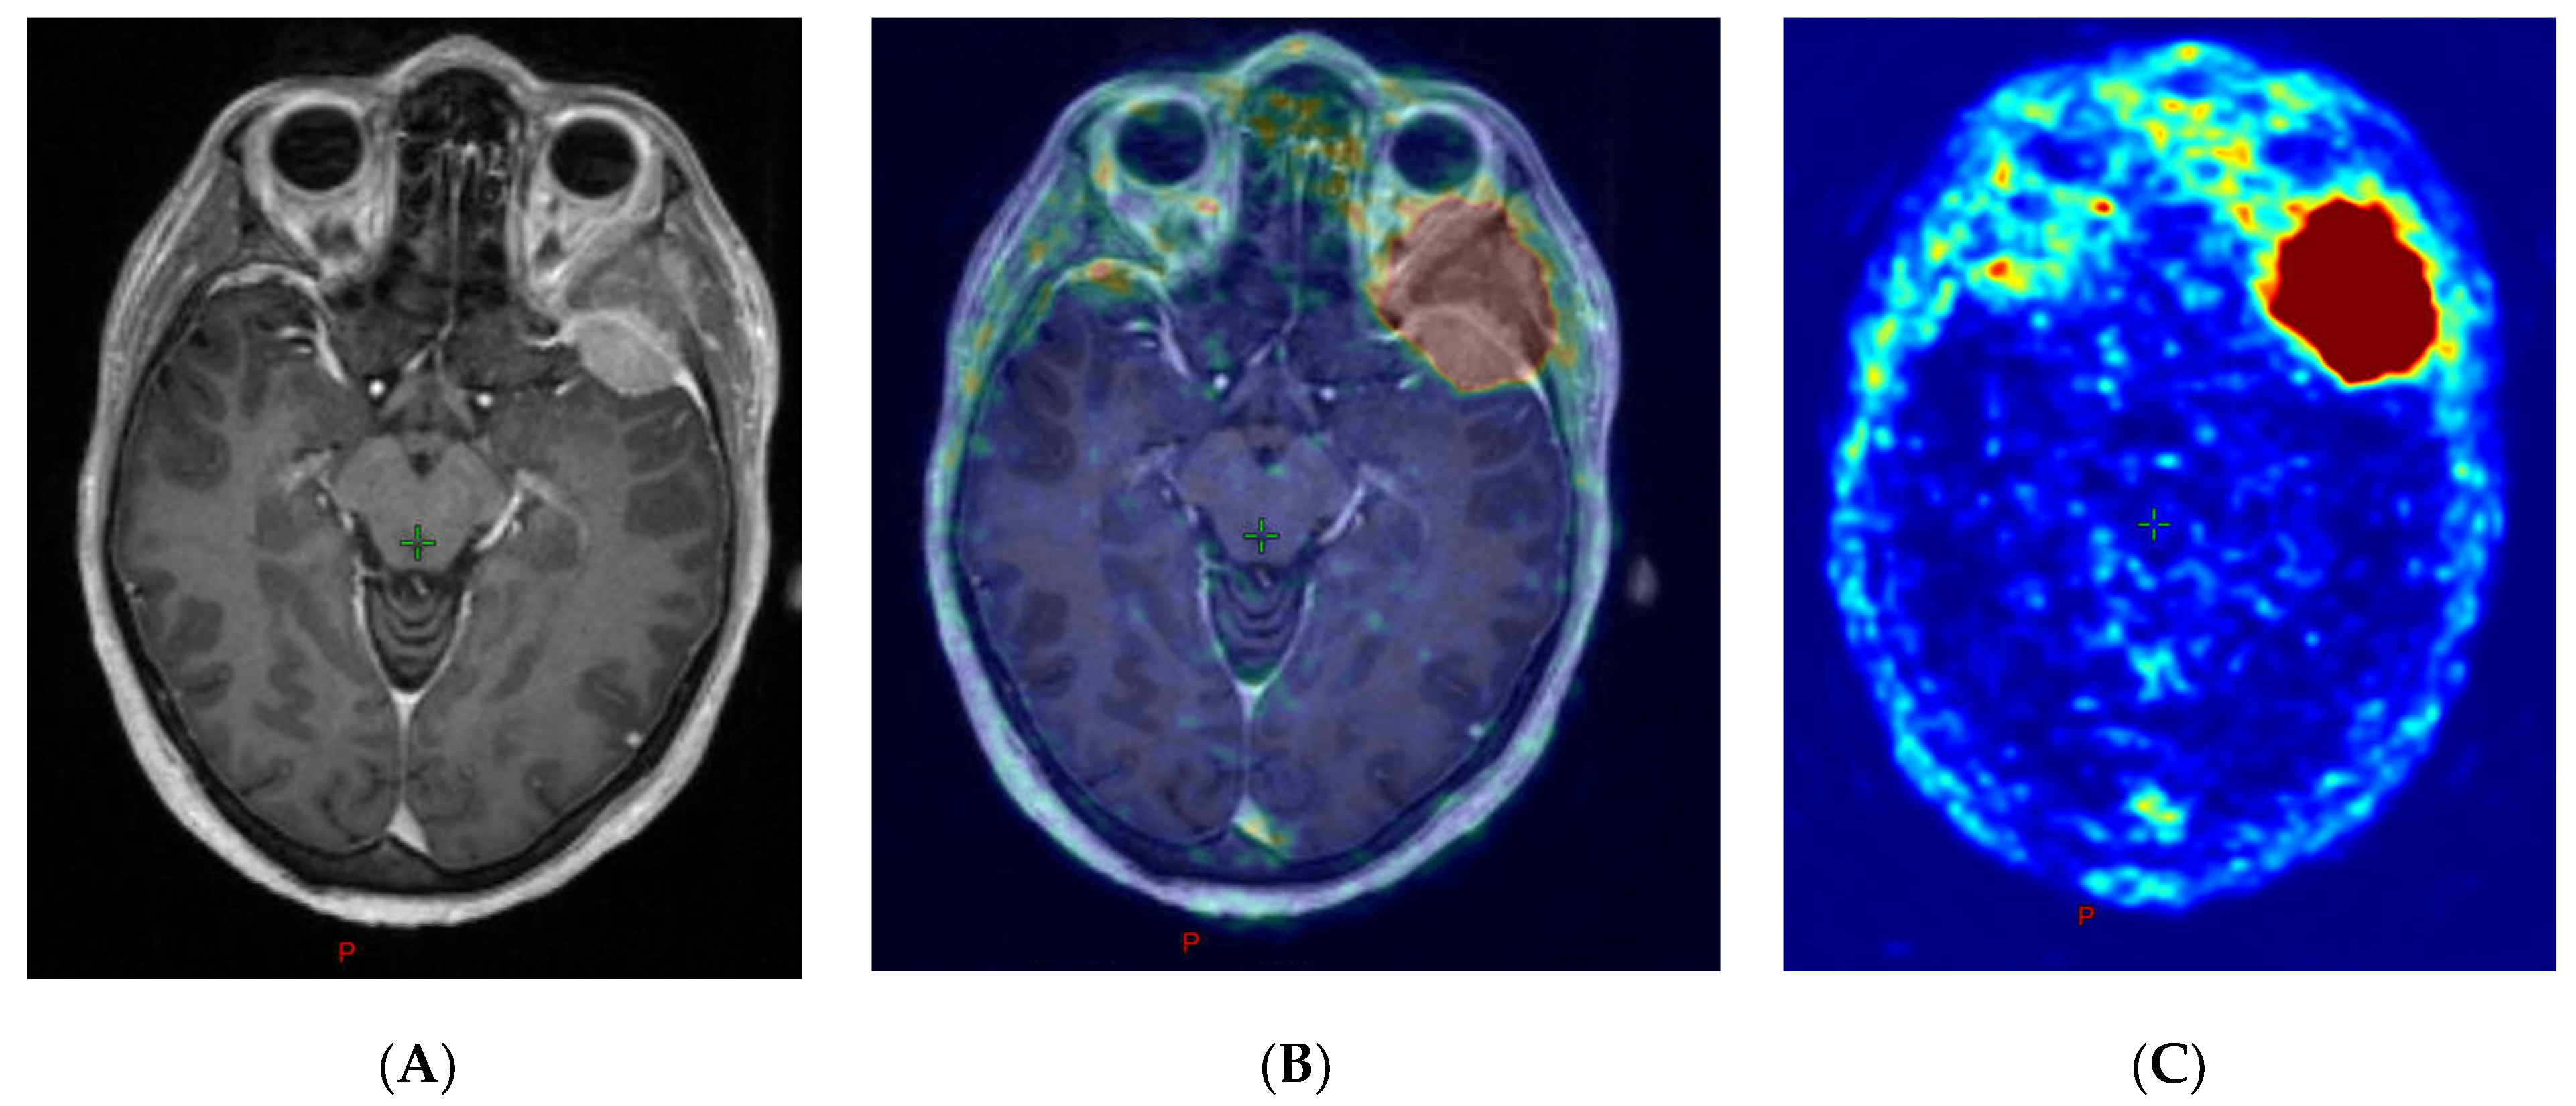

3.4. Lesion Assessment